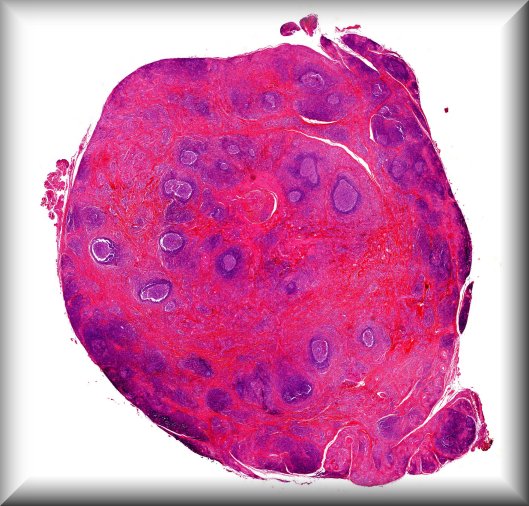

Rita Van Ginderdeuren (Leuven): Vitreous sample in chronic posterior uveitis, unresponsive to steroid treatment |